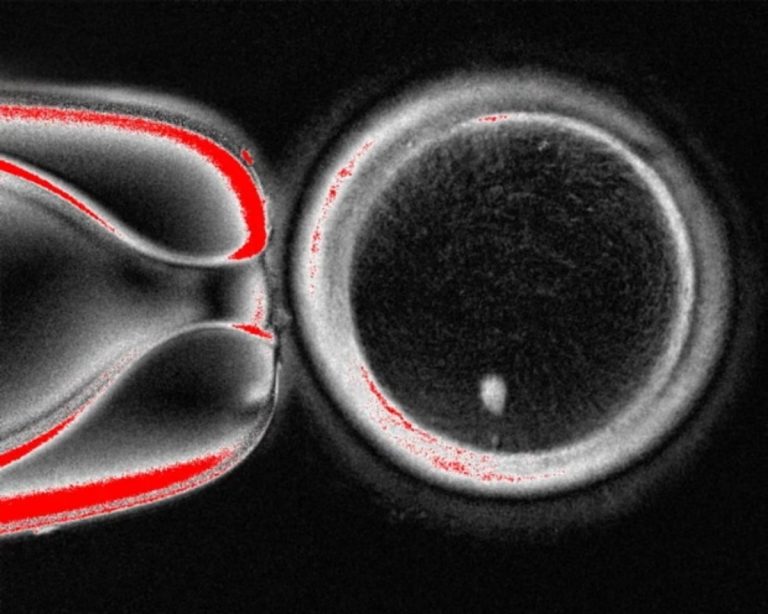

Η ομάδα του Όρεγκον ακολούθησε παρόμοια προσέγγιση, συλλέγοντας δερματικά κύτταρα από γυναίκες και αφαιρώντας τον πυρήνα από κάθε κύτταρο. Ο πυρήνας περιέχει τα 46 χρωμοσώματα που φέρουν περίπου 20.000 γονίδια που αποτελούν τον ανθρώπινο γενετικό κώδικα. Κάθε πυρήνας δερματικού κυττάρου τοποθετήθηκε σε ένα υγιές ωάριο δότη, του οποίου ο δικός του πυρήνας είχε αφαιρεθεί.

Σε άρθρο της που δημοσιεύθηκε στο επιστημονικό περιοδικό Nature Communications, η ερευνητική ομάδα περιγράφει πώς ξεπέρασε το πρόβλημα των χρωμοσωμάτων. Μετά τη γονιμοποίηση των ωαρίων με σπέρμα, τα ενεργοποίησαν χρησιμοποιώντας μια ένωση που ονομάζεται ροσκοβιτίνη. Αυτό είχε ως αποτέλεσμα τα ωάρια να μεταφέρουν περίπου τα μισά από τα χρωμοσώματά τους σε μια δομή που ονομάζεται πολικό σωμάτιο, αφήνοντας τα υπόλοιπα χρωμοσώματα να ζευγαρώσουν με αυτά του σπέρματος.